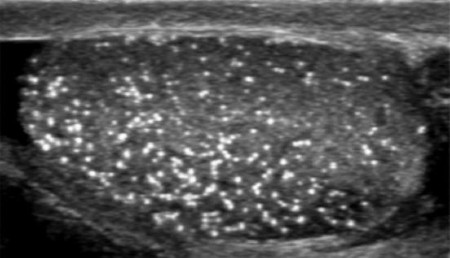

Μικρολιθίαση όρχεων

Η μικρολιθίαση (Εικ. 4) μπορεί να βρεθεί σε έως και το 9% των ανδρών που έχουν κάνει ένα υπερηχογράφημα του οσχέου για οποιονδήποτε λόγο. Είναι λίγο συχνότερη σε άνδρες με καρκίνο, κρυψορχία, στειρότητα, υπογοναδισμό και κιρσοκήλη.

Εικ.4: Μικρολιθίαση Όρχεων